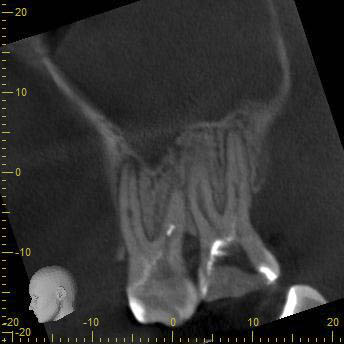

BN2627_DVT (13 von 17) Veröffentlicht 1. Dezember 2014 am 344 × 344 in Unerwartete Anatomie Zahn 26, 27- die WF